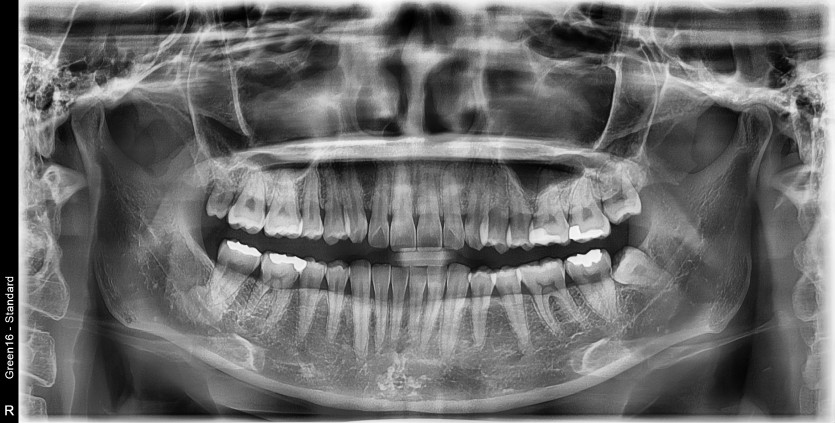

#38 사랑니 발치

구강 외과 전문의가 당일 발치했습니다.